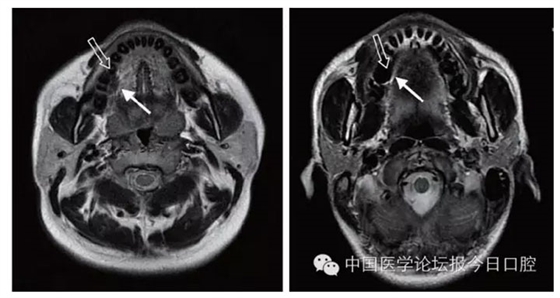

文獻(xiàn)研究中常使用的金屬包括鎳鉻合金、鈷鉻合金、低鈦合金、純鈦、金合金、金鈀合金、銀鈀合金等成分如表所示。大量研究得出近乎一致性的結(jié)論。金合金、金鈀合金、銀鈀合金對(duì)MRI影響甚微,與全瓷材料、丙烯酸樹(shù)脂極為相似,表現(xiàn)為修復(fù)體影像邊緣光滑、無(wú)變形、無(wú)偽影;純鈦金屬對(duì)MRI影響較小,接近于全瓷材料;但有的研究卻發(fā)現(xiàn)純鈦在核磁共振場(chǎng)中也產(chǎn)生偽影,但偽影涉及的掃描層數(shù)較少;低鈦合金(鈦合金)對(duì)MRI影響較大,介于純鈦和鎳鉻合金之間,中度偽影;鎳鉻合金、鈷鉻合金對(duì)MRI影響很大,鈷鉻合金更甚;表現(xiàn)為重度偽影、圖像扭曲變形(圖1、圖2)。不難看出,對(duì)MRI影響,全瓷材料、樹(shù)脂材料<金合金等貴金屬<純鈦<低鈦合金<鎳鉻合金<鈷鉻合金。有研究發(fā)現(xiàn)鈷鉻合金橋偽影大小與修復(fù)體長(zhǎng)軸一致,影響范圍為固定橋近遠(yuǎn)中徑2倍,頰舌徑的4倍;相同外形金屬修復(fù)體厚度增加,偽影增加。單個(gè)金屬樁核偽影可波及到上頜竇、牙槽骨、舌體、舌下腺等組織器官,但對(duì)眼底、眼內(nèi)容物、腦組織和頸椎成像基本無(wú)影響。

圖2 4種金屬冠在犬MRI檢查中的影響,圖片引自《實(shí)用口腔醫(yī)學(xué)雜志》2014第30期《4種金屬冠對(duì)磁共振成像影響的對(duì)比研究》一文,作者高嵐等